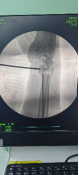

術前影像

患者男性,54歲,外傷致右側脛腓骨開放性骨折8小時,局部可見右側脛骨骨折近端露出···